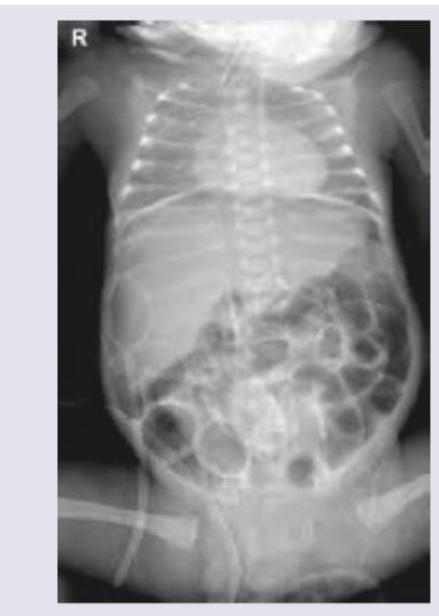

Question 9: Preterm child on cow milk due to death of mother is having blood in stools. X-ray abdomen was done. Diagnosis is:

- A. Rigler sign (Correct Answer)

Explanation: ***Rigler sign*** - Rigler sign (also called **double wall sign**) refers to **visualization of both sides of the bowel wall** on X-ray due to **free intraperitoneal air (pneumoperitoneum)**, indicating bowel perforation. - In the clinical context of a **preterm infant on cow milk with bloody stools**, this presentation is highly suggestive of **Necrotizing Enterocolitis (NEC) with perforation**. - The X-ray shows Rigler sign as evidence of pneumoperitoneum, a serious complication of NEC requiring urgent surgical intervention. - **Key NEC radiological findings** include: pneumatosis intestinalis (intramural gas), portal venous gas, and pneumoperitoneum (Rigler sign) in cases with perforation. *Double bubble appearance* - This sign shows **two distinct air-filled structures** (distended stomach and duodenum) on abdominal X-ray, indicating **duodenal obstruction** from duodenal atresia or annular pancreas. - Not associated with bloody stools or NEC in preterm infants. *Claw sign* - The claw sign is seen in **intussusception**, where the bowel telescopes into itself, creating a soft tissue mass with a crescent-shaped gas pattern. - Typically occurs in older infants (6-18 months), not preterm neonates, and presents differently from NEC. *Bird of prey sign* - This sign is associated with **sigmoid or cecal volvulus**, showing a distended bowel loop with a beak-like configuration. - Represents large bowel obstruction, not the typical presentation of a preterm infant with feeding intolerance and bloody stools from NEC.